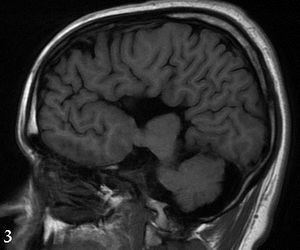

A rare finding is a timely lesson for all clinicians who are touched in one way or another by the injectable drug crisis in the US.